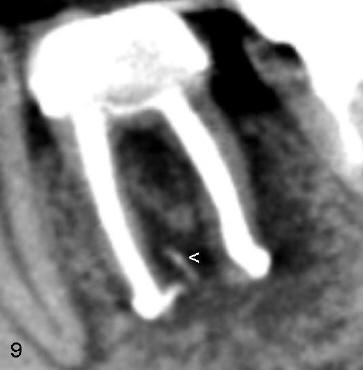

It is most likely that leaking of sodium hypochlorite (1.25%) and Chloroform through the enlarged pre-existing apical foramina causes temporary chemical burning of the inferior alveolar nerve through the abnormal communication and also by gravity. Mechanical mechanism such as extruded GP (< in Fig.9) is less likely.